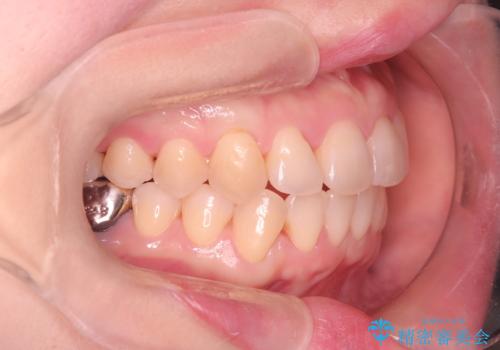

- 前歯の翼状捻転の改善を希望してこられた患者様です。

下顎の叢生はインビザラインで解決することがきましたが、上顎の捻転が完全には改善できなかったため、上顎は途中からワイヤーを用いて治療を行っています。

捻転の改善はインビザラインで苦手とするところですので、うまく治らない場合はワイヤーを提案しています。